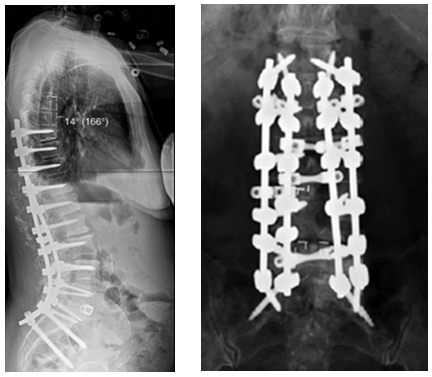

图7 术前-术后1个月-术后1个月外观

(4)固定棒选择

图8-11 相关文献表明,钴铬合金可提高固定强度及融合率,防止断棒,但也增加了PJK的发生率